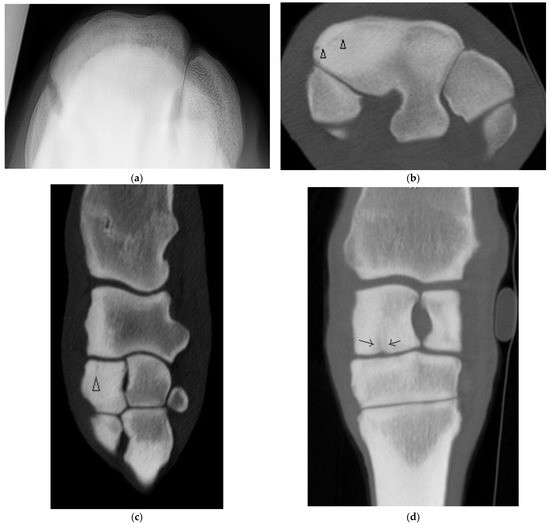

Four horses had complete fractures of variable configuration with both sagittal and frontal components. Three were corner Fx of the RaF and two of these had substantial additional fissures or fractures detected only on CT (Figure 4). The other horse had a complete Fx of both facets, with orientation that was sagittal in the RaF and frontal palmar to the InF (Figure 5); a configuration not recognized on DR.

Figure 4. Images of the left carpus of a 6-year-old thoroughbred gelding. (a) Transverse CT image through the proximal portion of the distal row of carpal bones. A comminuted corner fracture of the radial facet of the third carpal bone (C3) is evident. (b) A transverse CT image further distad reveals a large frontal fissure (arrow head). (c) Flexed dorsoproximal-dorsodistal oblique radiographic view of the distal row of carpal bones. The comminuted corner fracture was evident radiographically but the frontal fissure was not.

Figure 5. Images of the right carpus of a 3-year-old standardbred filly. (a) Flexed dorsoproximal-dorsodistal oblique radiographic view of the distal row of carpal bones. There is a vague sagittal lucency surrounded by sclerosis within the radial facet (RaF) of the third carpal bone (C3). A fracture was suspected but the configuration was unclear. (b) Transverse CT image through proximal C3. CT imaging confirmed a complete slab fracture of C3 that is sagittal within the RaF then courses in a frontal plane palmar to the intermediate facet (arrow heads). The fracture passes through a moderate sized subchondral lucency within the RaF.